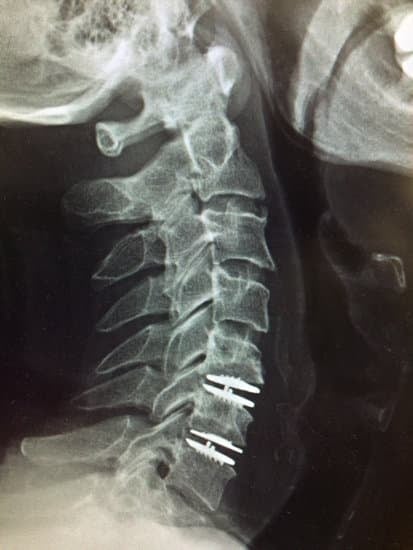

경추 인공디스크 치환술은 일반적으로 목 앞쪽을 통해 접근하여 수행됩니다.

수술 중에는 손상된 디스크를 제거하고, 인공디스크를 삽입하여 디스크의 기능을 대체합니다.

이 인공디스크는 경추의 정상적인 움직임을 유지하고 주변 디스크에 대한 부담을 줄여줄 수 있습니다.

4. 인공디스크 삽입

손상된 디스크를 제거한 후, 측정과 평가를 통해 환자에게 가장 적합한 인공디스크를 선정합니다.

이 인공디스크는 경추의 자연스러운 움직임을 모방하도록 설계되었으며, 삽입 과정은 정밀하게 수행됩니다.